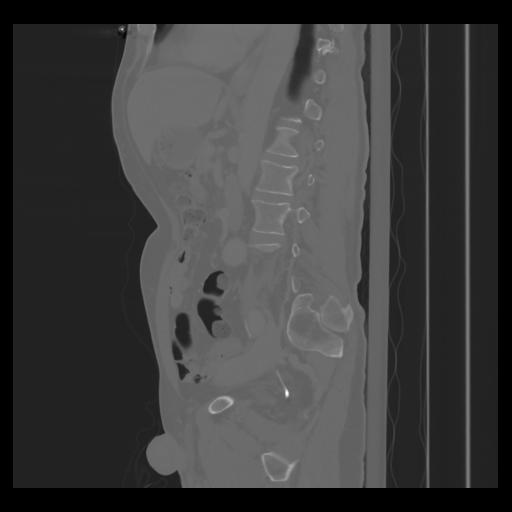

36 CUERPO,CE,Sagittal,3.000,CUERPO,Sagittal,